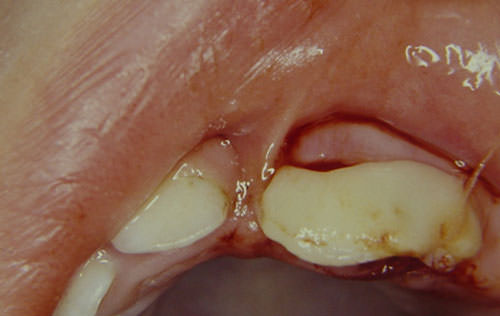

En la anamnesis la madre relató que la caída había ocurrido una hora antes, cuando el niño intentaba subir las escaleras de casa. Se realizó el examen clínico minucioso de los tejidos blandos para verificar la presencia de hemorragia, tumefacción o presencia de cuerpos extraños. Se observó laceración de tejidos blandos, una coloración rojiza de los tejidos periodontales en la región de los dientes anteriores (51, 61 y 62), con sangrado discreto alrededor del diente 61 y dislocación hacia fuera de su alveolo, corona levemente desviada hacia palatino y presencia de movilidad. El traumatismo fue diagnosticado como luxación extrusiva (Figura 1). No se diagnosticó fractura de hueso alveolar a la palpación.

Figura 1

Fotografía inicial. Sangrado discreto alrededor del diente 61 con dislocación hacia fuera de su alveolo.